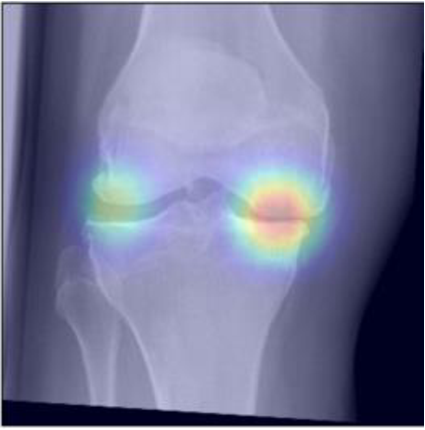

To gain insight into the basis of the CNN’s prediction, we used the GradCAM [24] approach and visualized the attention maps for the well-predicted knees. Examples of attention maps are presented in Figure 5. We observed that in various cases, the CNN paid attention to the compartment opposite to the one where degenerative change became visible during the follow-up visits. Additional examples of such attention maps are presented in Supplementary Figures 3, 4, 5 and 6.

Refer to caption

(a)

(b)

(c)

(d)

Figure 5: Examples of attention maps for progression cases and the corresponding visualization of progression derived using follow-up images from MOST datasets. Here, subplots (a) and (c) show the attention maps derived using a GradCAM approach. Subplots (b) and (d) show the joint-space areas from all the follow-up images (baseline to 84 months). Here, the subplot (b) corresponds to the attention map a) and the subplot (d) corresponds to the attention map (c).